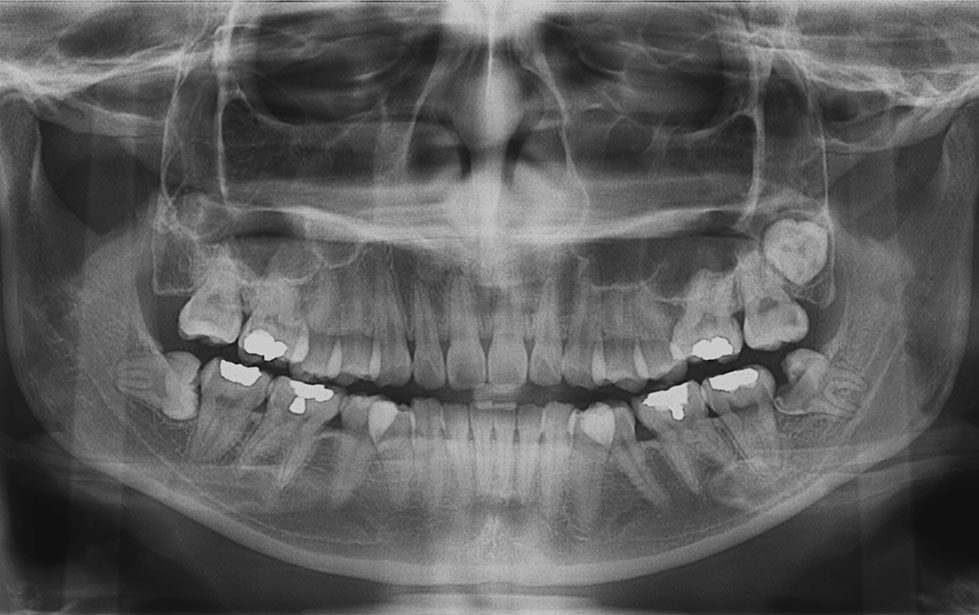

AI X-ray Detection & Automated Dental Charting

Ever wonder what your dental x-ray really shows? With our AI technology, you can now see it more clearly than ever.

The AI analyses your x-ray images within seconds and highlights areas that may need attention, such as tooth decay, impacted tooth, bone loss and etc. These are shown directly on your x-ray image, helping you understand what is going on at a glance.

The system also automatically updates your dental chart, which is part of your dental records, saving time and ensuring every detail is properly recorded.